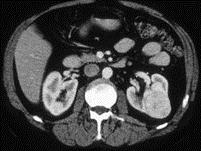

问题 女,47岁,左侧腰部隐痛不适2 月余,请结合下列图片作出诊断 ( )

选项 A、左肾炎性包块 B、左肾感染性囊肿 C、左肾血管平滑肌脂肪瘤 D、左肾出血性囊肿 E、左肾癌

答案 E